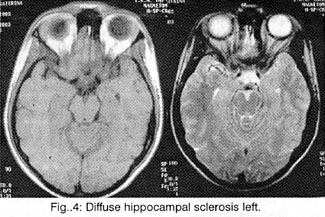

But the most important task of the Neuroimaging is (always in connection to the clinic) the help to the localisation of the lesions (which provoke the epileptic seizures), to the differential diagnosis of this lesion among hereditary illnesses (phacomatoses, leukodystrophies), abnormalities of development (dysplasias, vascular malformations, neuronal migration disorders: heterotopia-double cortex syndrome (Fig. 1), schizencephaly, lissencephaly, unilateral Megalencephaly), perinatal cerebral injuries (between the 30th week of pregnancy and the end of the first month of life due to placental insufficiency, hypoxia, infections, intoxication and mechanical birth trauma4, presented as porencephaly, focal or generalized enlargement of the ventricular system or the subarachnoid space (Fig. 2), hippocampal sclerosis (Fig. 3 and 4) or acquired lesions (benign or malign neoplasms, cerebrovascular diseases, encephalitis (Fig. 5), cerebral abscess, parasitic, fungal and protozoan diseases (Fig. 6), cerebrocranial injuries, degenerative diseases), for the best coping with the patient's problem (conventional pharmaceutical or neurosurgical treatment), as well as for the prognosis before and after the preferred therapy.